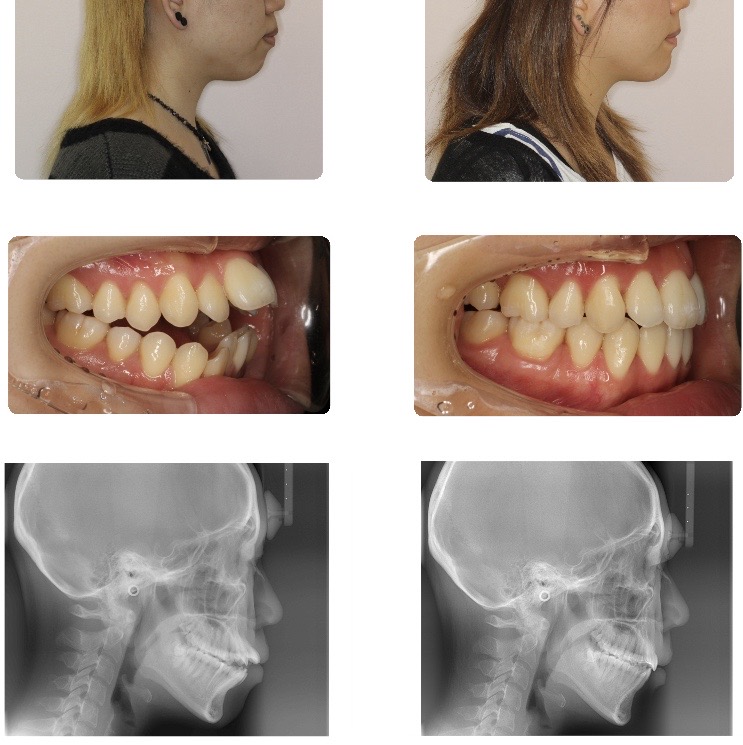

反対咬合(受け口)

上顎の歯が乱ぐい歯で、かつ反対に咬み合っていました。

矯正治療後は、歯並び・咬み合わせともに満足いく状態に整えられました。

歯みがきもしやすく、効率よく咀嚼できる咬み合わせになっています。また反対咬合の改善から、口元のバランスも改善しました。